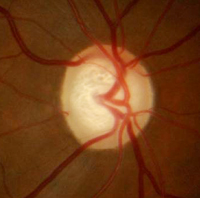

Il nervo ottico è costituito dall’insieme delle fibre nervose (circa un milione) che connettono la retina al cervello. La sua funzione è quella di trasmettere gli impulsi generati a livello retinico fino al cervello. Nel glaucoma si ha una perdita progressiva di queste fibre, con un conseguente quadro di atrofia del nervo.

A sinistra: nervo ottico sano. A destra: nervo ottico con atrofia glaucomatosa